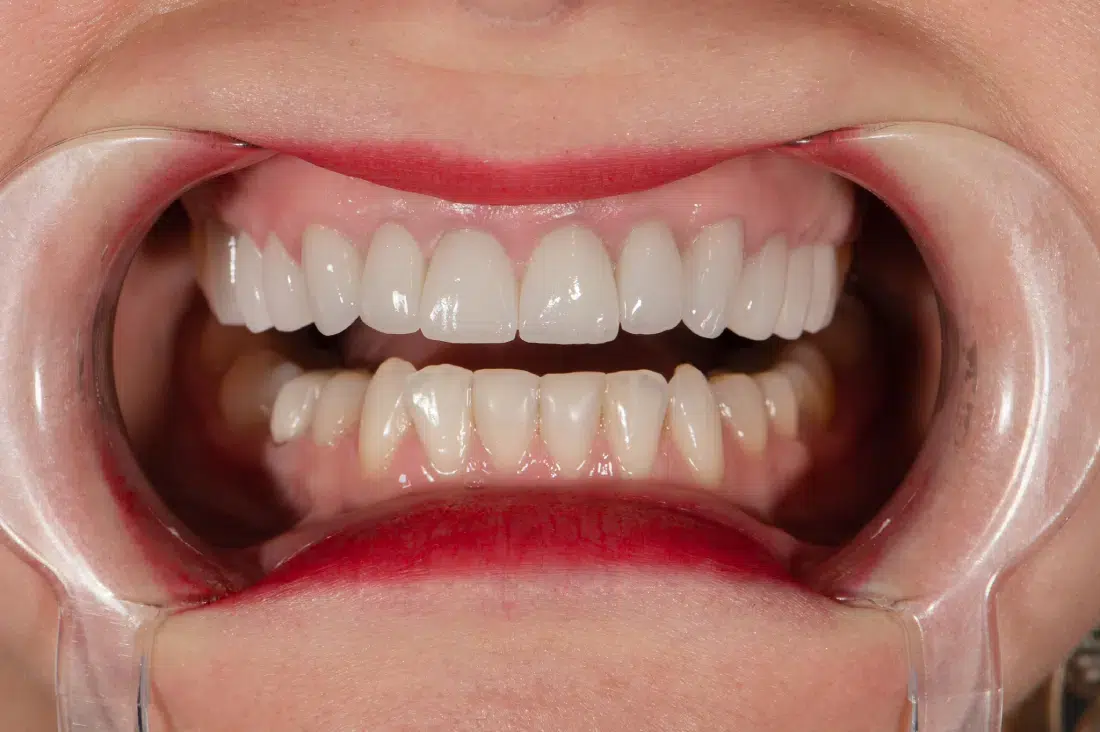

Caz de estetică dentară – Fațete ceramică presată E-Max

Provocarea acestui caz a fost în prepararea minim invazivă a dinților centrali rotați și a obține o formă și o culoare cât mai naturală, pacienta dorind un caz de estetică dentară ce să nu fie observabil.

Pacienta a beneficiat de corecție gingivala cu laser pentru uniformizarea asimetriilor gingivale, tratamente endodontice de canal sub microscop, obturațiile vechi (plombe) schimbate cu materiale de compozit cu particule nanoceramice, și fațete dentare din ceramică presată E-Max.

Termen de finalizare 2 săptămâni de la amprentarea finală.